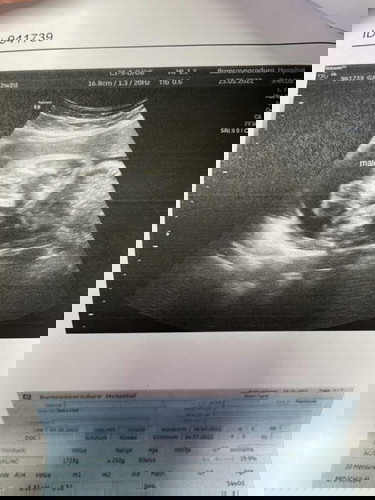

บ้านนี้ก็รอลุ้นรอบ 2 เหมือนกันค่ะ ว่า จะ ญ หรือ ช เพราะซาวด์รอบแรกเค้าหนีบไว้ คุณหมอบอก 60% ญ ถ้าซาวด์รอบนี้ไม่เห็นก็ไม่เป็นไร ขอให้เค้า แข็งแรง ออกปลอดภัย อวัยวะครบก็ดีใจมากแล้ว 🥰

บ้านนี้รู้ตอนได้6เดือนจ้า กว่าจะได้รู้หนีบไว้เหมือนดันค่ะ ตอนนี้31+3ค่ะ บ้านนี้ได้ลูกสาวค่ะ กำหนดคลอดกรกฎาคมเหมือนกันค่ะ

บ้านนี้ซาวดูหลายรอบขาหนีบสะนิดเรยค้ะดุยากมาก รอลุ้นอีกวันที12เดือนหน้าจะให้เห่นอีกไหม จะ8เดือนล้ะยังม่รุเพศเรย

ยินดีด้วยจ้า บ้านนี้ 32w +1dยังไม่รุ้เพศเลย น้องหนีบไว้ตลอดเลย

เหมือนกันเลยค่ะ ซาวทุกรอบที่หมอนัดขาหนีบสะนิดทุกรอบ จะเข้า8เดือนล้ะยอใจลุกเรย😂

รบกวนแม่ที่พอดูเพศออก ดูให้หน่อยค่ะ